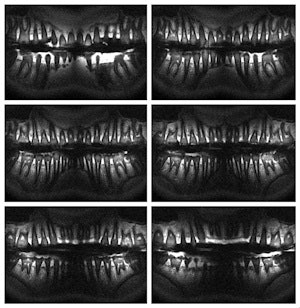

These images show that by placing the MRI loop in the occlusal plane, the teeth and jaw bones are well positioned within the sensitive volume of the coil. All images courtesy of Djaudat Idiyatullin, University of Minnesota.

Noting that the most comfortable coil position -- the occlusal plane -- has not been seriously considered in previous dental MRI studies, the researchers set out to demonstrate the advantages of using a loop coil in the occlusal position for dental imaging.

"In the occlusal position ... the sensitive volume of the coil encompasses the most important dental structures -- the teeth and their supporting structures -- while uninteresting tissues containing much higher proton density (cheeks, lips, and tongue) are outside the sensitive volume," they wrote.

The resulting images are the first MRI panoramic images to demonstrate high nominal resolution (0.3 mm3), the researchers noted. The images show that the teeth and jaw bones are well positioned within the sensitive volume of the coil, while the signal from the cheek and tongue yield low intensity, they added.